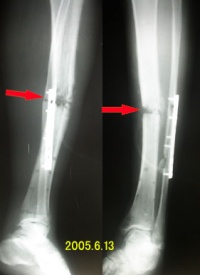

(四)固定术

严重的胫骨干开放性骨折伴有广泛的软组织损伤,或需进行植皮或广泛的整形手术。2.同侧肢体多发骨折,伴有股骨干骨折和其他大的创伤者。3.胫骨多段骨折,中间段骨片有移位者。4.胫骨干骨折,骨片失落,造成骨缺损者。5.胫骨干骨折经闭合整复治疗,不能达到满意效果,有旋转或成角移位者。

胫腓骨骨折的早期治疗有不同观点,大致三种,一、所有骨折均早期作内固定;二、所有骨折均用闭合方法治疗;三、一般用闭合方法,如有特殊指征,也可早期作手术整复和内固定。胫骨下1/3位于皮下,甚至前内侧均处于皮下,且胫骨的血供亦较其他有丰富肌肉包围的骨骼为差,故延迟愈合,不愈合和感染是最常易发生的并发症,切开重定内固定是治疗胫骨干骨折的有效方法之一。